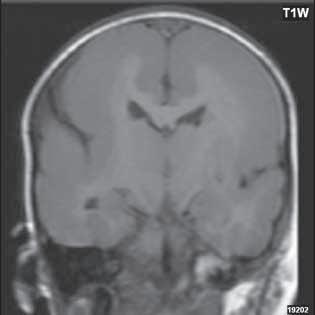

Při agenezi corpus callosum CT i MR zobrazí paralelní průběh postranních mozkových komor (oproti fyziologickému

konvergentnímu průběhu) a jejich oddálení, časté rozšíření okcipitálních rohů – colpocefalie, někdy středočárový lipom, cystu. Koronální řezy ukážou rozšíření frontálních rohů postranních komor, III. komora je situována vysoko mezi postranní komory, tvoří jakoby trojzubec, který někteří autoři přirovnávají k přilbě Vikinga. Není patrné septum pellucidum. Častá je přítomnost středočárového lipomu nebo cysty.

Obr. I.1.2a Paralelní postavení postranních komor, kolpocefalie, ageneze corpus callosum

Obr. I.1.2b Ageneze corpus callosum

Obr. I.1.2c Ageneze corpus callosum, frontální rohy postranních komor mají tvar rohů na Vikingské helmě, kraniálně uložená III komora